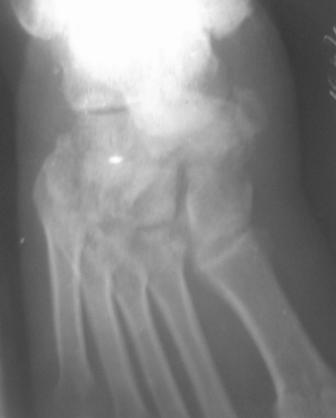

[Ortho] Застарелый вывых ладьевидной кости стопы

Правильные снимки.

По  данному  случаю,  оказалось  3  месяца  назад  было  произведена Р-графия в  райбольнице,  но  больной предпочел  лечится  у  табиба. Присылаю  первичные  снимки.